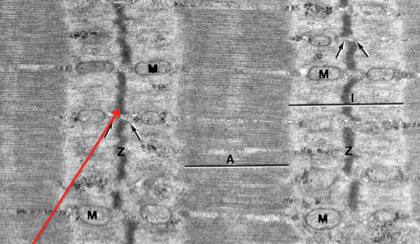

z band

M band